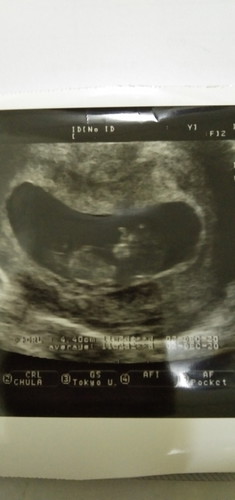

วันนี้โดนฉีดวัคชีลมาปวดมากคะแต่ก็เป็นความเจ็บที่งดงามวันนี้อายุครรภ์ได้11วีคเต็มน้องขยับตัวได้แล้วแม่ดีใจมากถึงจะยังมองไม่ชัดแต่แม่ก็ดีใจตื่นเต้นเพราะท้องแรกคะแต่น้ำหนักแม่ขึ้นมาเพียงโลคึ่งเท่านั้นคะแม่ๆว่าน้อยไปไหมค่ะเพราะช่วงนี้แม่ทานข้าวไม่ค่อยได้แพ้ท้องคะ